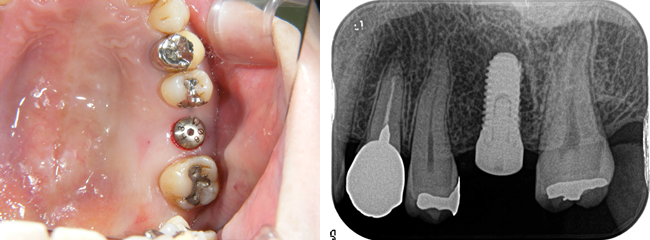

インプラントと骨が結合したら、歯型を採って、歯冠になる部分を作ります。

下の写真は、ジルコニアという素材です。ネジで固定します。

ネジで固定するシステムですので、咬み合わせの面に穴が開いています。

専用のレンチでネジを締めます。

ネジ穴を詰め物でふさいで完成です。